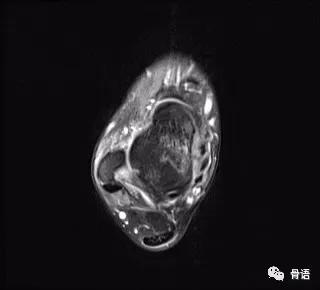

图1 患者术前MR轴位片

图1、图2示术前ATFL连续性中断、显影模糊,提示ATFL撕裂,距骨软骨损伤,骨髓水肿。图3、图4示ATFL关节镜下带线锚钉固定联合PRP治疗术后6个月ATFL完整性存在,张力好,骨髓水肿信号较前减轻。该患者术后随访效果满意,症状较前明显减轻。